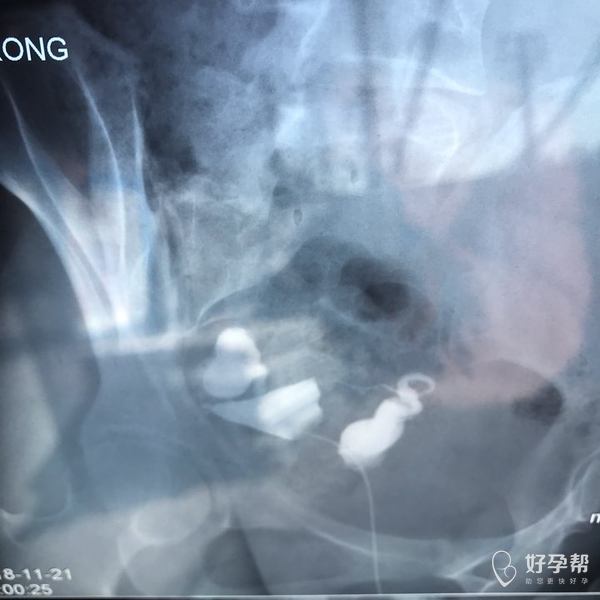

麻烦各位教授给我看看输卵管造影片子,谢谢了🙏

您好,输卵管堵塞,建议切除输卵管做试管,保守保守治疗没有多大意义,觉着我的回复对您有帮助记着帮忙点击采纳,谢谢!